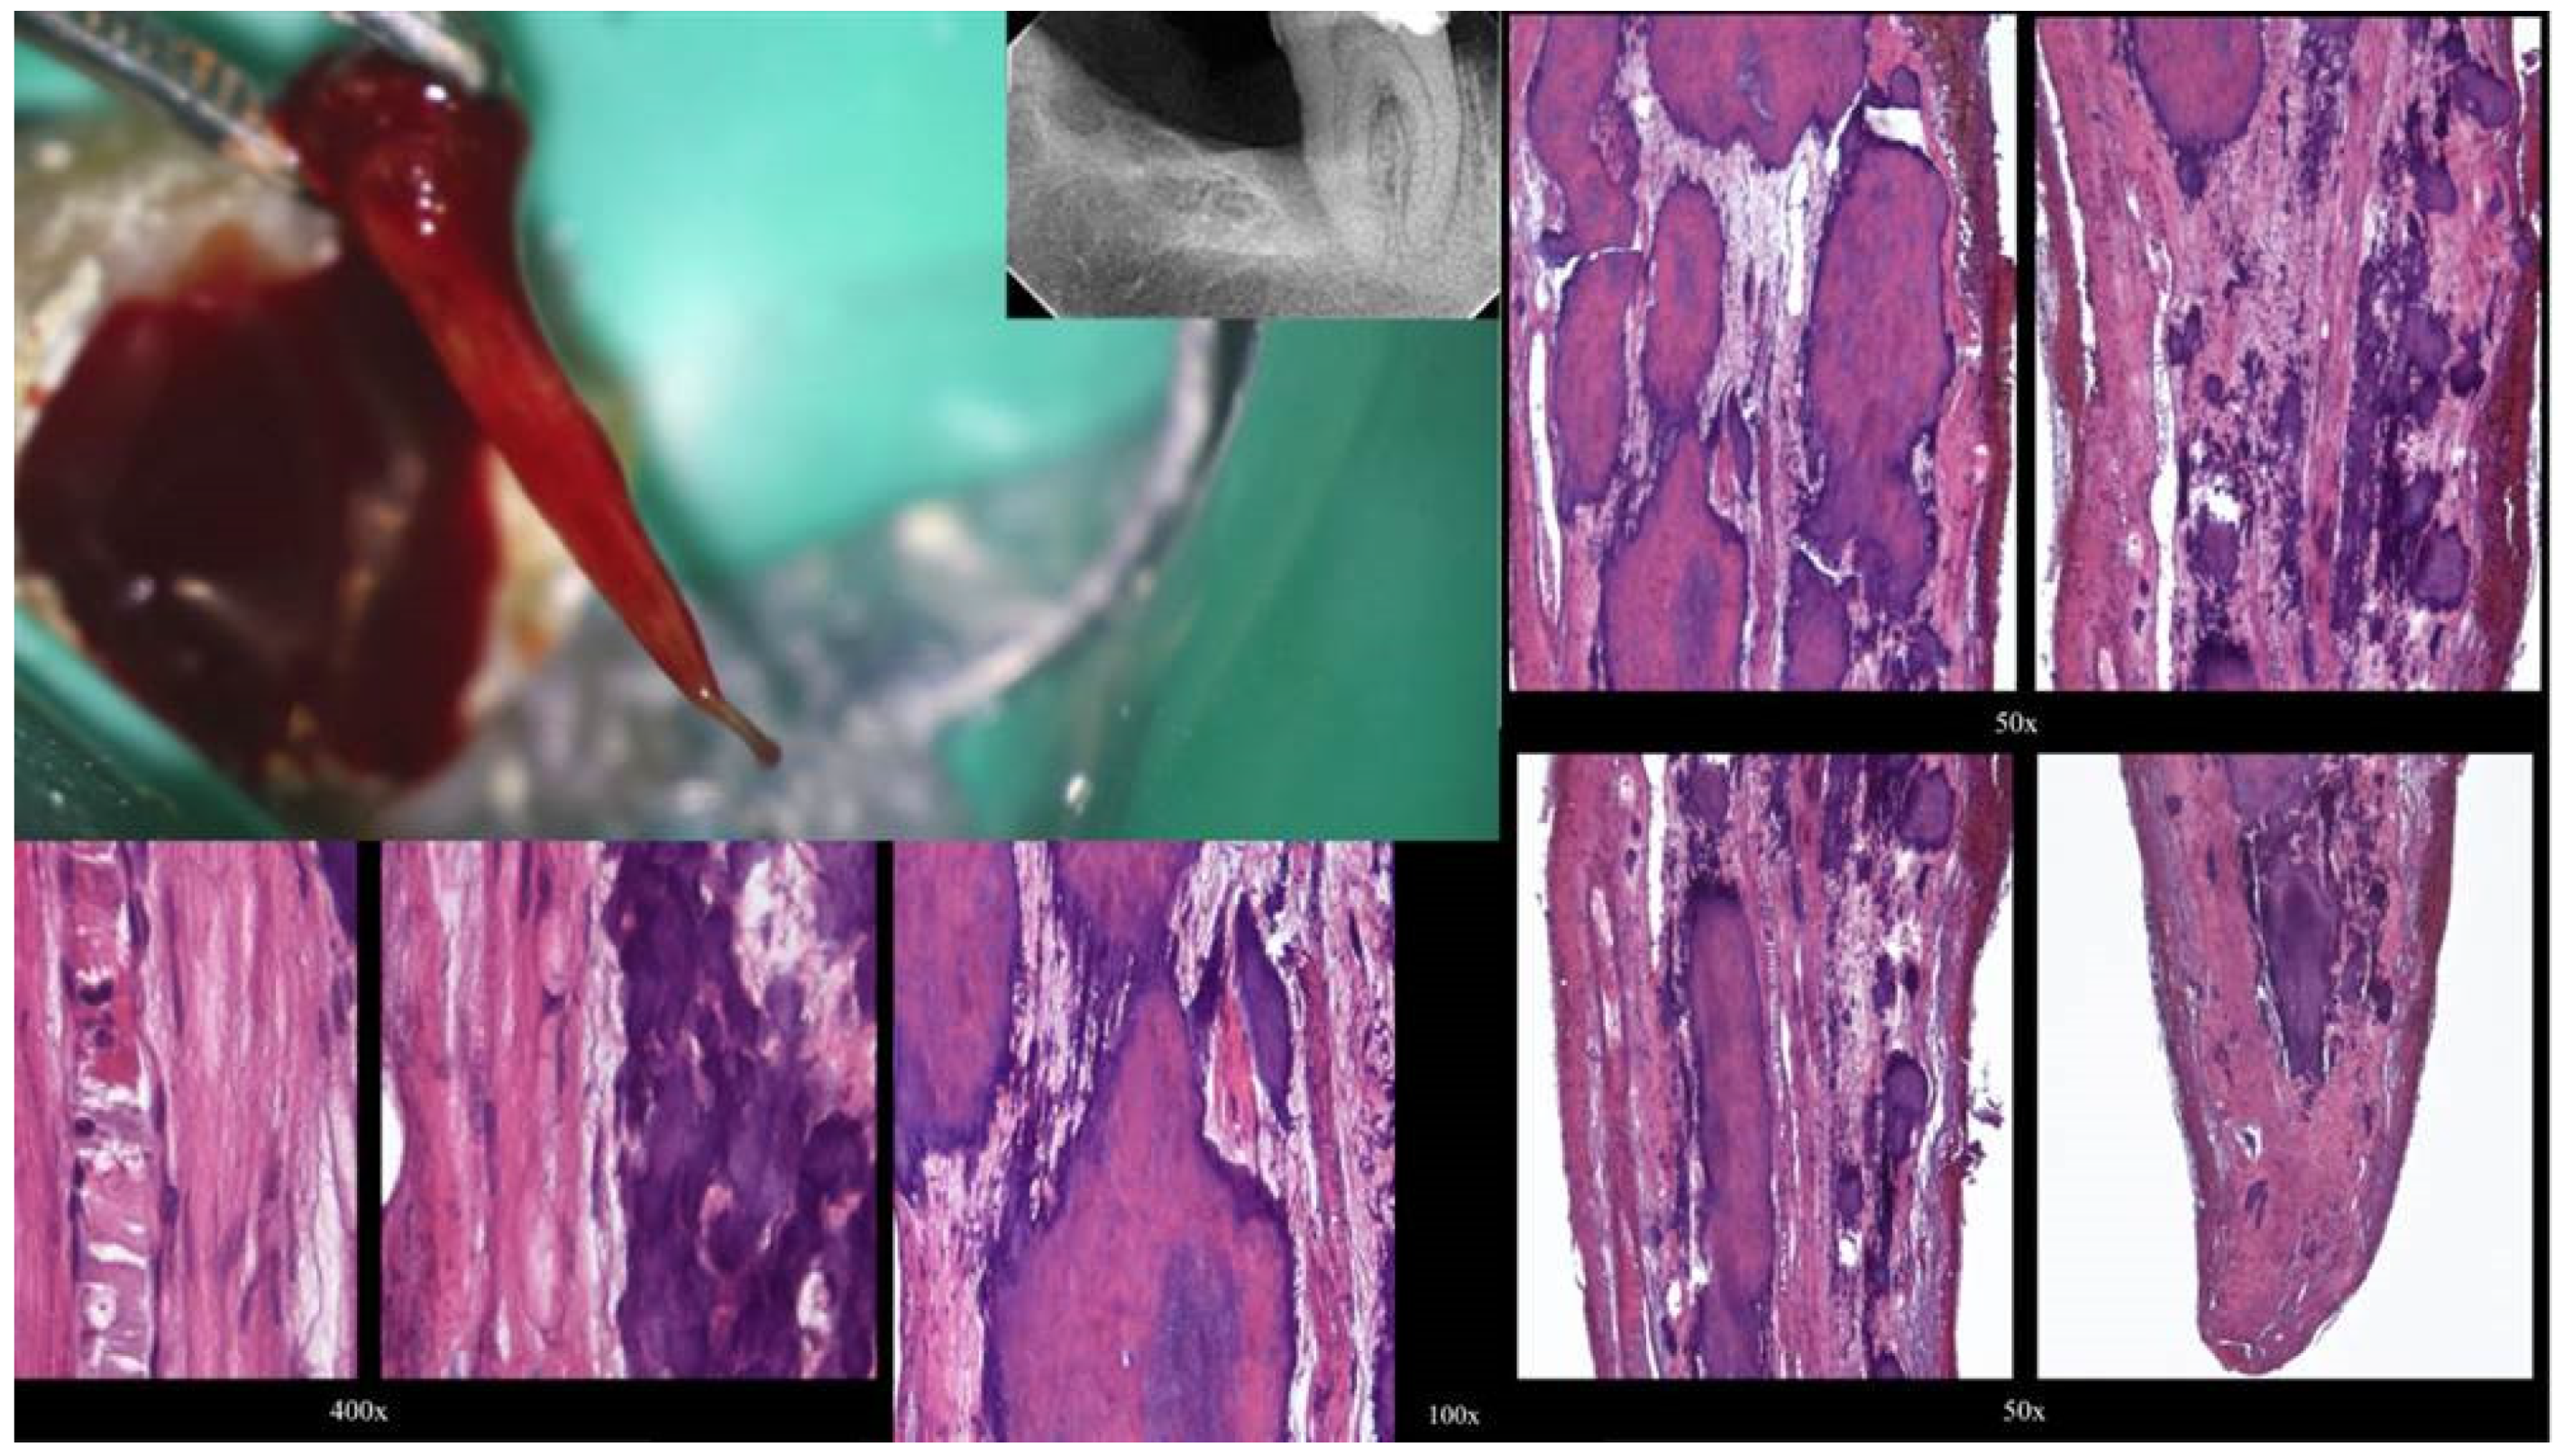

Figure 9.

(A) Radiographic image of an extracted partially calcified maxillary premolar. (B) Magnified view at the level of the axial cut (a grey area in a). (C,D) Creation of initial access dimple in the white spot indicating the calcified orifice. (E) Continuous chelation of the cut dentinal surface (F,G). An initial unsuccessful attempt to negotiate the calcified canal orifices with D-finder files iso 08. (H) Fitting of the tip of an EDM file (Hyflex EDM-one file, Coltene) in the dimple without activation. (I,J) On-spot buckling resistance activation test (BRAT) negotiation of the EDM files. (K) Negotiation of the 08 d-finders inside the calcified canals after the BRAT negotiation technique removed coronal calcified canal obstructions. (L) Radiographic verification of calcified canal negotiation (images and radiographs courtesy of Dr. Chaniotis Antonis).

The initial dimple is deepened progressively in a crown-down sequence until a patent pathway is met and confirmed (Figure 9 and Figure 10).

Buckling resistance activation test (BRAT) negotiation is defined as the activation of an engine-driven file with an active or dynamic tip against the conditioned calcified tissue that is blocking the canal trajectory (Figure 9 and Figure 10). The tip of the engine-driven instrument is attached to the calcification point without activation. The instrument is activated according to the manufacturer’s instructions, and the file is pushed in an axial direction against the calcification (long press and release). The lateral buckling movement of the file is restrained by the canal walls. When the progression of the file is achieved, the file is removed from the canal, and the canal is checked for patency with a hand file. If patency is achieved, then standard root canal treatment procedures can be continued. If there is no patency, the same procedure can be attempted deeper inside the calcification. The step-by-step progression of a rotary file through the calcification with the BRAT technique is described in Figure 10.

In Figure 11, Figure 12, Figure 13 and Figure 14, initial negotiation through the calcified canal orifices was carried out using the BRAT technique until canal patency was met. The conditioning of the calcified tissue blocking the canals for the BRAT technique to be effective is preferably accomplished with the continuous chelation concept.